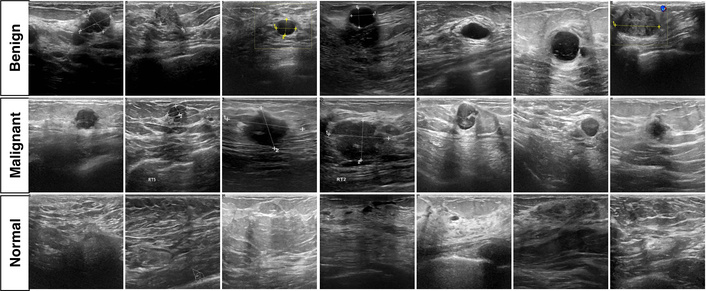

Figure 1 provides representative examples from each class to illustrate the visual variability encountered in BUSI. In general, benign lesions often present more regular margins and relatively homogeneous echotexture, whereas malignant lesions more frequently show irregular borders and heterogeneous internal appearance. Normal examples are included to reflect typical background parenchymal patterns. The figure also highlights common ultrasound characteristics such as speckle and limited contrast, which contribute to the difficulty of the classification task.

Representative BUSI examples for malignant, benign, and normal categories. BUSI: Breast Ultrasound Images.